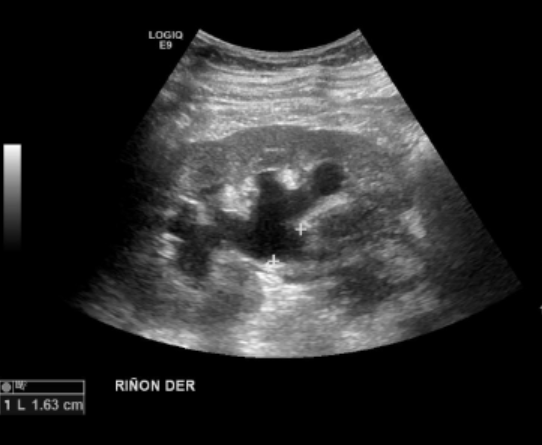

Se observa el riñón derecho aumentado levemente de tamaño con una hidronefrosis moderada. Adyacente al riñón se observa una masa isoecogénica respecto a la cortical renal, heterogénea, de bordes mal definidos, con señal periférica al Doppler, de presunto origen ureteral.

Riñones de forma y tamaño normal. Presentan buen espesor en su parénquima y adecuada delimitación entre este y el seno renal. No hay dilatación pielocaliciaria izquierda ni imágenes categóricas de cálculos renales bilaterales. Existen quistes simples parapiélicos renales izquierdos, el de mayor tamaño, mide 12 mm.

Moderada hidronefrosis derecha, secundario a lesión sólida pieloureteral, hipoecogénica y heterogénea. Mide 6,2 x 4,8 x 8,1 cm, vascularizada.

Moderada hidronefrosis derecha, secundaria a la lesión pieloureteral, de aspecto primario.